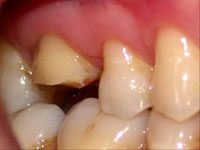

O dente 16 apresentava apenas duas cúspides remanescentes e fragilizadas, as quais precisaram ser reduzidas por desgaste (Fig. 1). Após a redução cuspídea, restou uma coroa clínica curta e com assoalho pulpar plano. Devido a essas condições não havia a possibilidade de preparar uma caixa oclusal, os degraus proximais que determinam uma cavidade MOD pois a polpa seria atingida , assim como, estrutura para reter uma coroa total. (Fig. 1, 2 e 3).

Fig. 1

Vista intra-bucal por oclusal do dente 26 mostrando as cúspides mésio-vestibular e mésio-palatina fragilizadas.